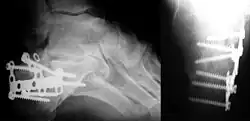

Röntgenbild einer Fersentrümmerfraktur mit Verplattung